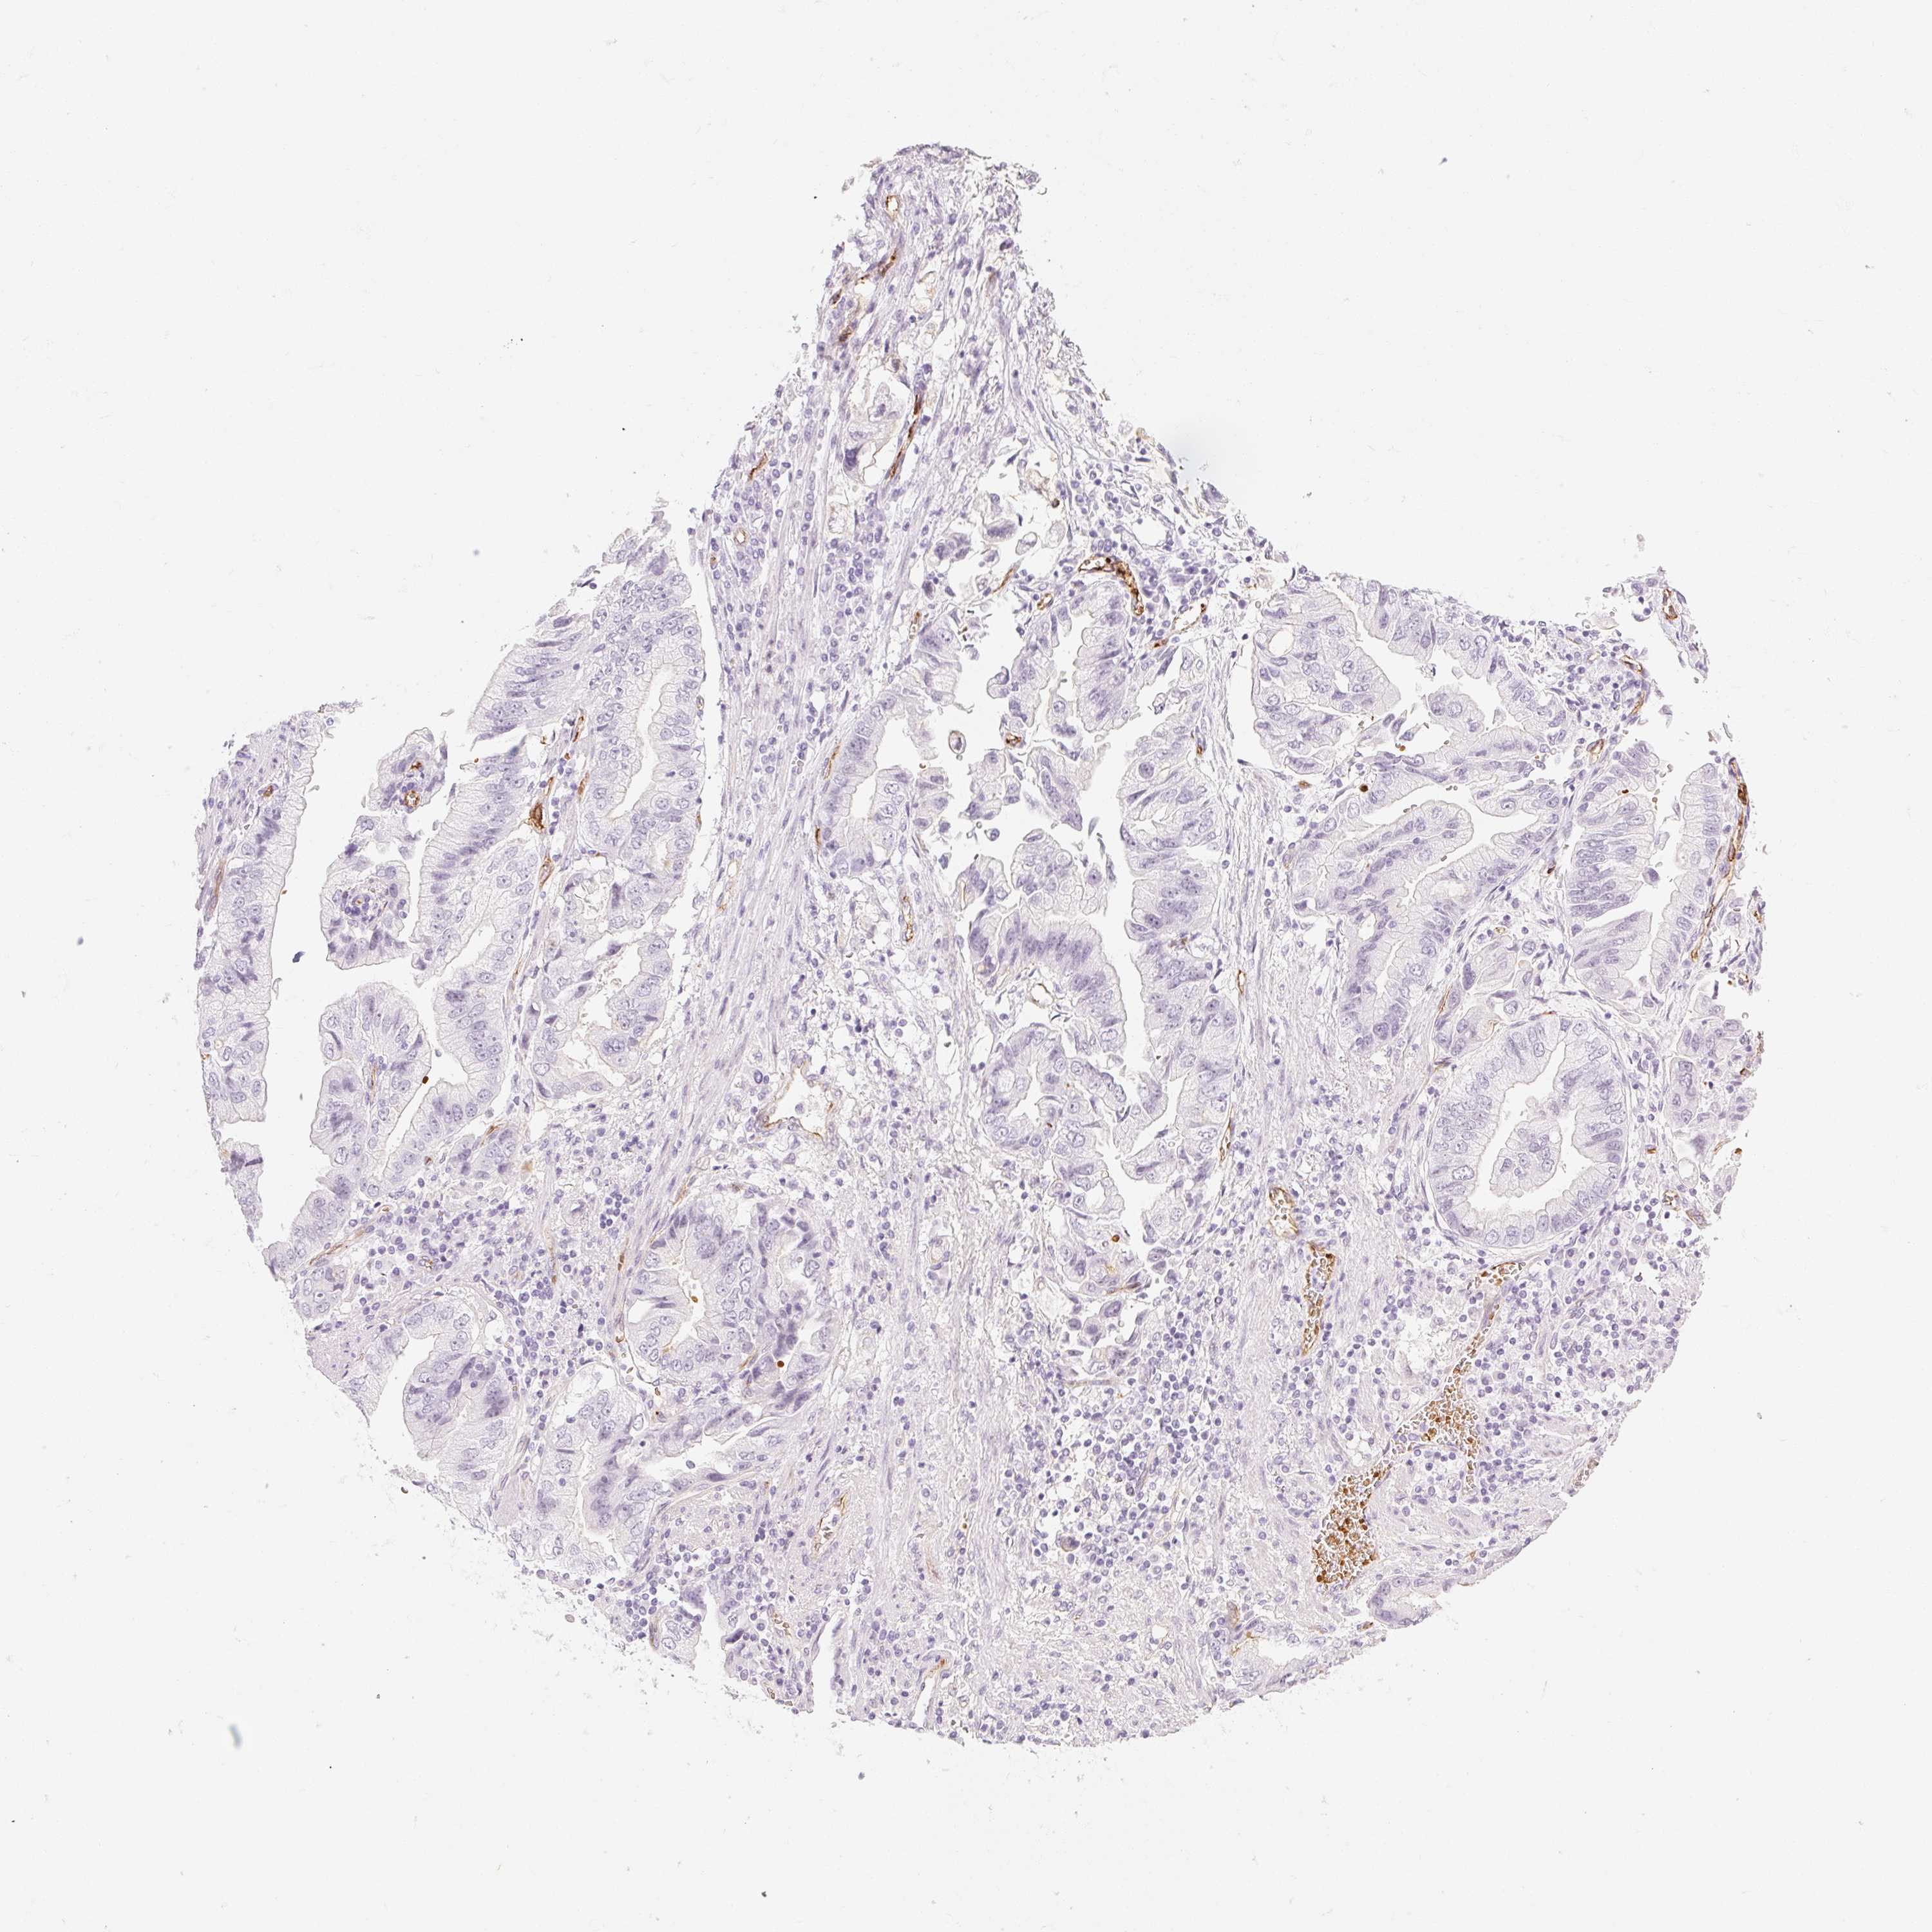

STOMACH CANCER - Protein expressioni

A mouse-over function shows sample information and annotation data. Click on an image to view it in a full screen mode. Samples can be filtered based on level of antibody staining by selecting one or several of the following categories: high, medium, low and not detected. The assay and annotation is described here.

Antibody stainingi

Antibody staining in the annotated cell types in the current human tissue is reported as not detected, low, medium, or high, based on conventional immunohistochemistry profiling in selected tissues. This score is based on the combination of the staining intensity and fraction of stained cells.

Each image is clickable and will lead to virtual microscopy that enables deeper exploration of all samples and also displays staining intensity scores, fraction scores and subcellular localization as well as patient and tissue information for each sample.

Antibody HPA056605

Staining

High

Medium

Low

Not detected

Intensity

Strong

Moderate

Weak

Negative

Quantity

>75%

75%-25%

<25%

None

Location

Nuclear

Cytoplasmic/membranous

Cytoplasmic/membranous,nuclear

Adenocarcinoma, NOS